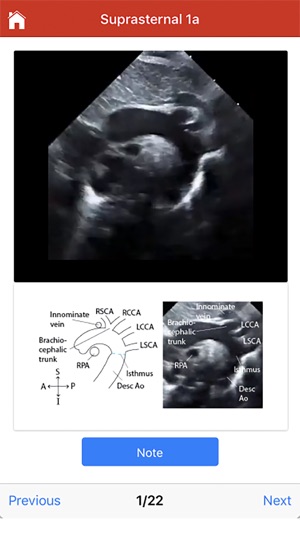

This educational tool, developed in connection with the University of Wisconsin-Madison, provides procedural guidance for performing a normal pediatric echocardiogram. The system delivers instructional content organized by four standard imaging views: subcostal, parasternal, apical, and suprasternal. To facilitate skill acquisition, the platform integrates multimedia assets, including video clips, static images, and technical illustrations. A user can navigate through a protocol sequentially or access specific views directly. Procedural instructions are displayed automatically upon view selection and can be supplemented with additional notes accessible through the interface.